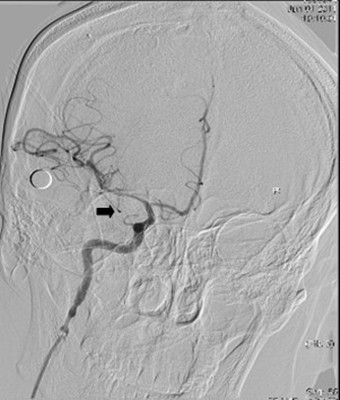

图2:取栓后见右侧颈内动脉开通,大脑前及大脑中动脉显影良好

考虑患者年轻,一般情况可,建议可急诊行介入下脑动脉内取栓手术。经患者家属同意后,急诊行全脑血管造影,造影见患者右侧颈内动脉颅内段于眼动脉处成残端,右侧大脑中动脉和右侧大脑前动脉均未见显影,即患者是右侧大脑半球全部缺血,病情危重,命悬一线,取栓需要分秒必争。最终经过约2小时的急迫手术,我神经内科介入小组成功从患者颅内血管闭塞处取出多枚栓子,总共约2CM长,实现颅内血管完全再通(见图1-3)。